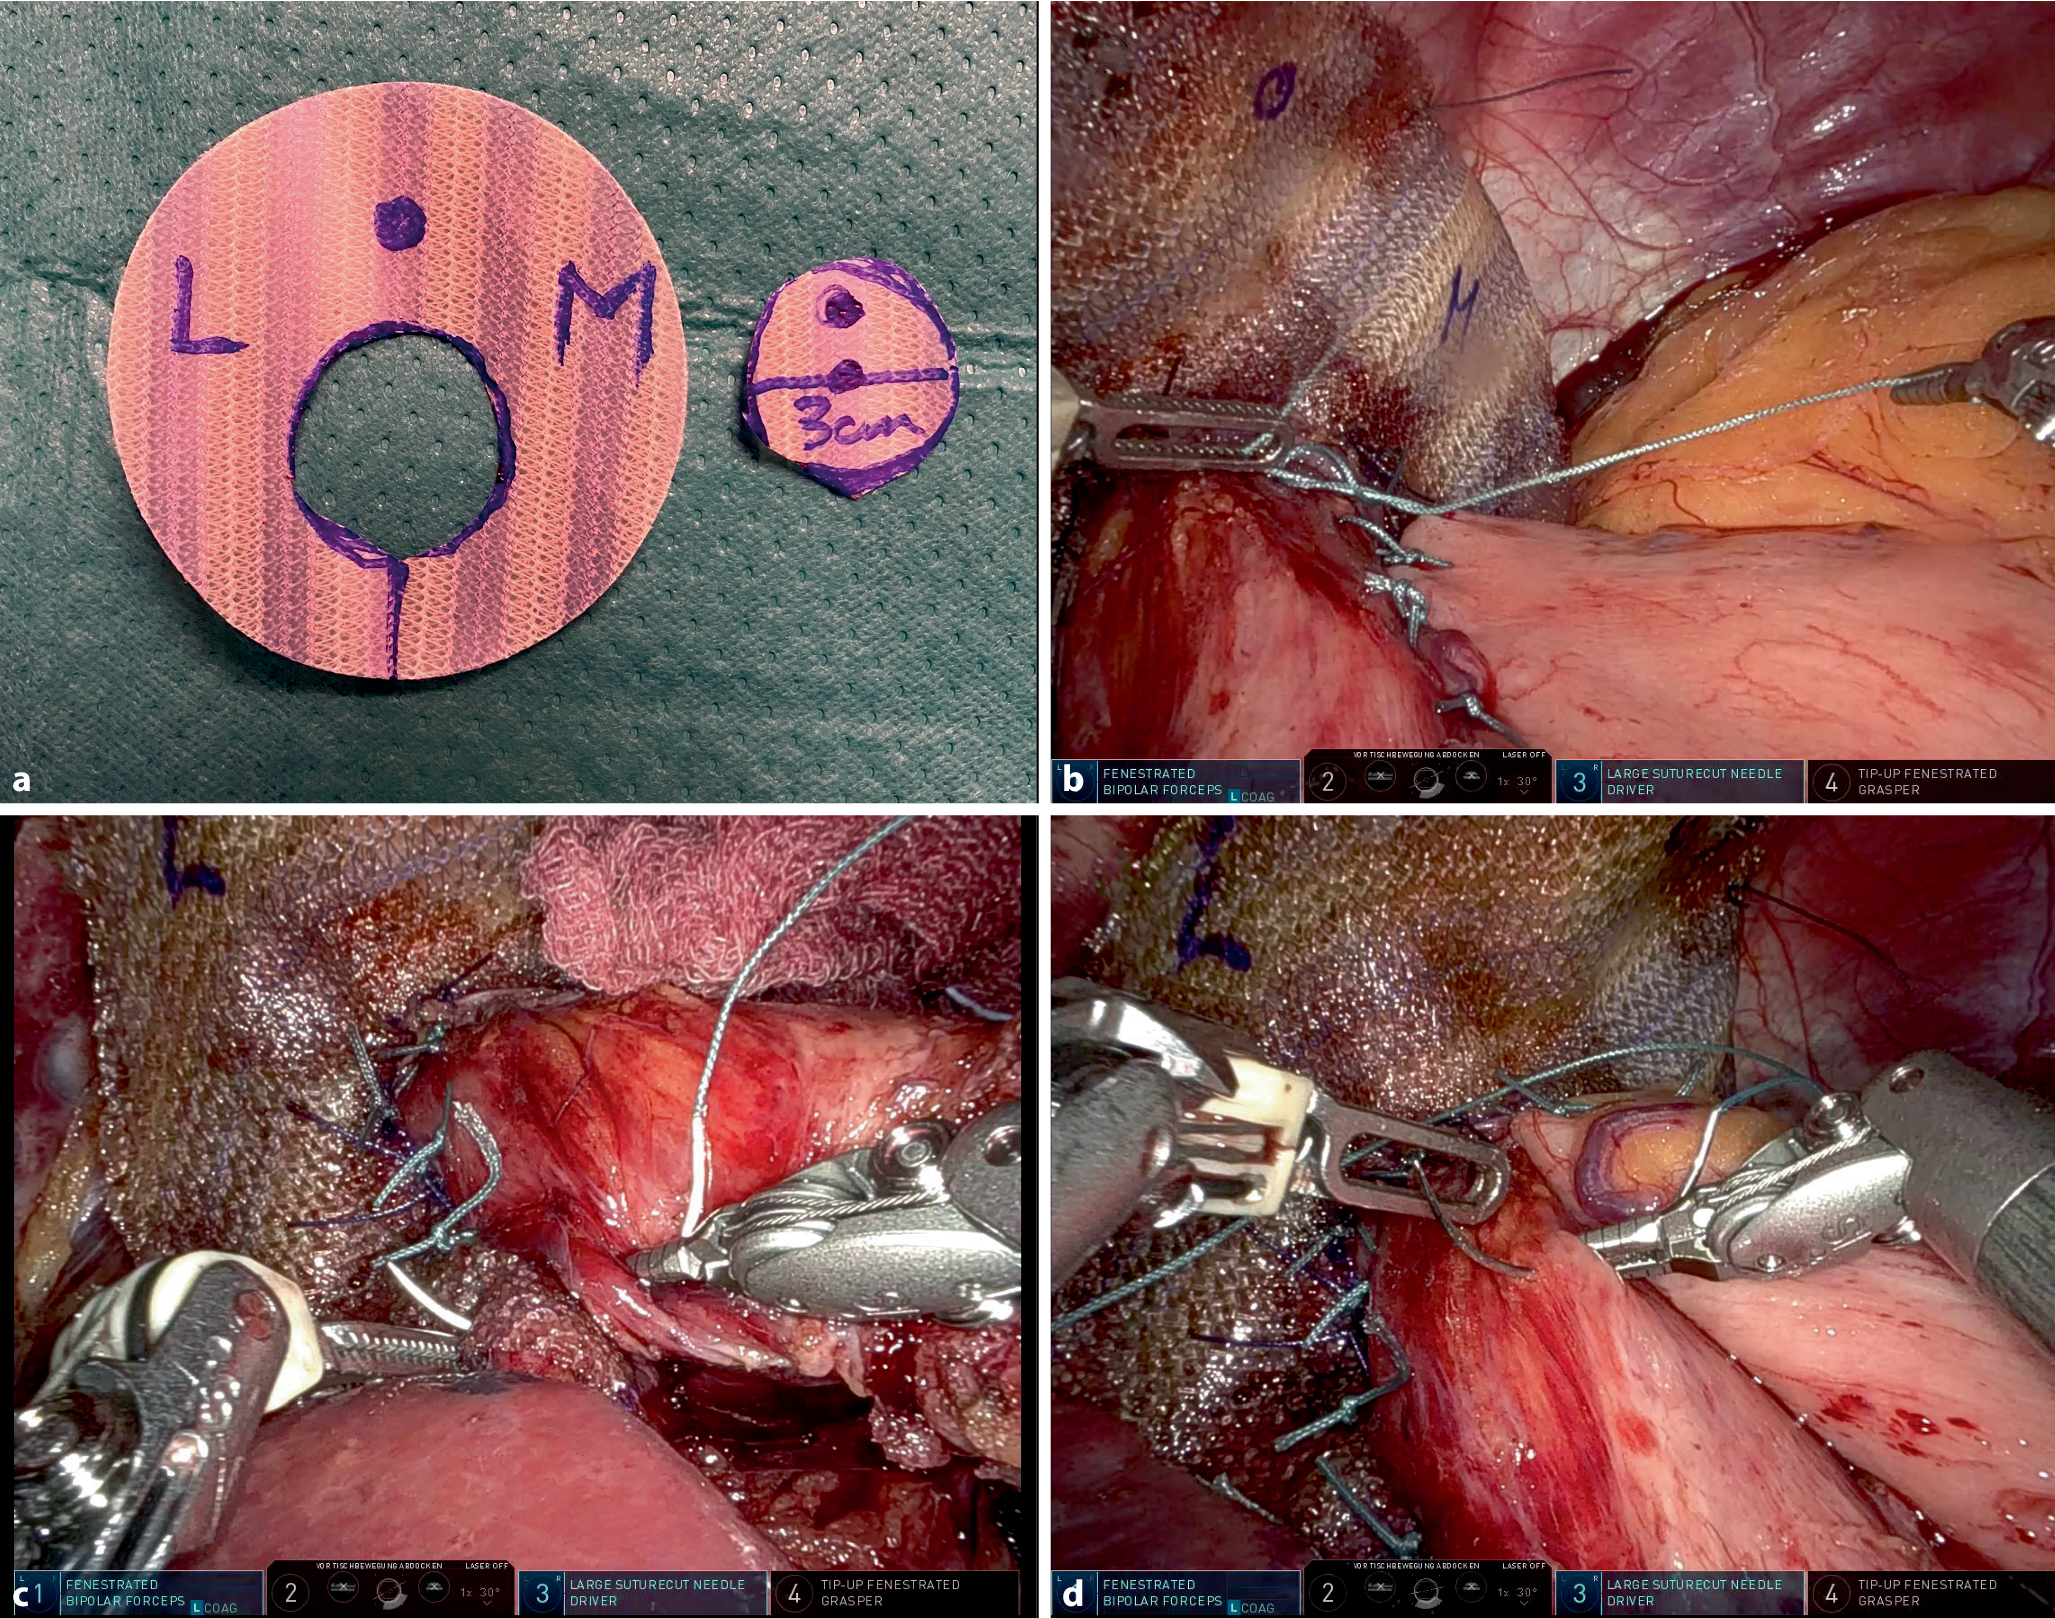

Traditional HH repair often involves either posterior or anterior crurorrhaphy, with the choice typically guided by defect anatomy and surgeon preference. Posterior repair is more commonly employed. In our practice, we optimize hiatal closure by “low-tension triangulation” for both anterior and posterior hiatal closure, aiming to minimize tension and improve repair durability. For this, we conceptualize the hiatus defect as a triangle. Closure begins at the posterior crural convergence. As we proceed anteriorly, the angle formed by the posterior crura naturally widens and, simultaneously, the tension on the knots increases. Once the posterior crural angle approaches 90°, we initiate anterior suturing (either right or left, depending on individual anatomy). This anterior placement in turn reduces the posterior angle, thereby decreasing tension and friction at the knot. We alternate between anterior and posterior suturing until optimal hiatus closure is achieved (as illustrated in Fig. 1). In our personal experience, robotic surgical platforms significantly enhance this technique, allowing for more precise and secure suture placement within the often-restricted space of the hiatus. This precision contributes to more robust primary repair, potentially improving long-term outcomes for patients.

Fig. 1

Hiatal closure demonstrating “low tension triangulation.” Subfigures ae illustrate a stepwise technique, starting posteriorly and transitioning to anterior sutures as needed, leading to optimal crural closure (f). Illustrations are paired with intraoperative images

Mesh augmentation and “anatomical reconstruction” of the esophagogastric junction (EGJ). a Keyhole-shaped biosynthetic absorbable mesh (Phasix™, BD, Franklin Lakes, New Jersey, USA). The low placement of the recess for esophageal passage ensures broader anterior hiatal mesh coverage. L liver, M Milz (German for spleen), and ventral dot for proper orientation. b His-angle reconstruction following the Lortat–Jacob technique. c Anchoring the esophagus and EGJ to the hiatal crura (modified Hill gastropexy). d 90–180° anterior partial fundoplication